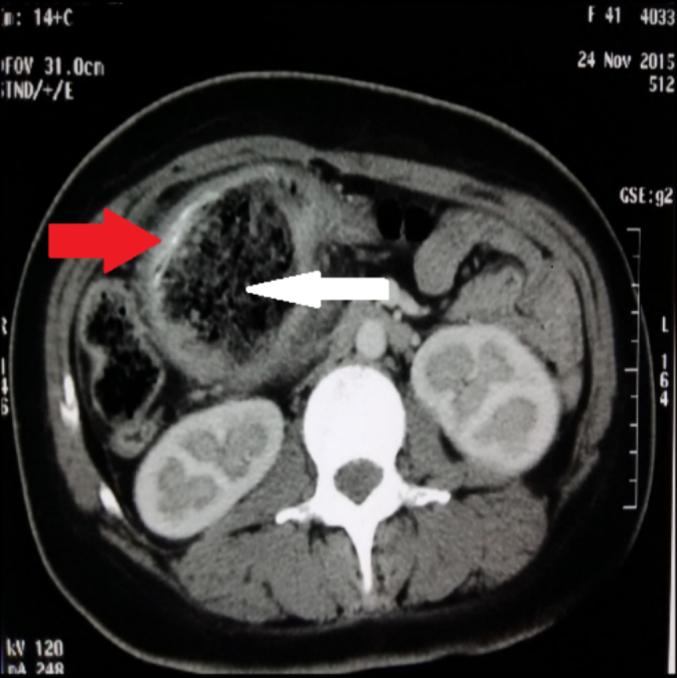

Textilomas are an infrequent but well-known surgical complication. The authors report a series of cases to describe the frequency of abdominal textilomas, the circumstances in which they occur, their clinical and morphological characteristics, and their management, to contextualise these data, which may serve as a basis for preventive measures.

Twenty-one (21) cases of abdominal textiloma were collected, with an annual frequency of 2.1 cases/year. The cases were predominantly female, with a female-to-male sex ratio of 1.62. The median age of the patients was 37 years. The initial operation was performed in a public facility in 80.95 % of cases. Myomectomy was the main indication (23.81 %). The time for signs to develop before consultation was 16.47 ± 8.82 days. Textiloma extraction was performed in an emergency in 61.90 % of cases. We noted morbidity (38.10 %) and mortality (9.52 %) in our patients.